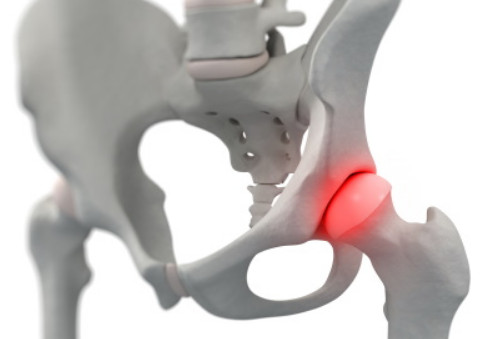

고관절 통증 원인 ④ 고관절 충돌증후군

뼈 돌출이 고관절 충돌을 유발할 수 있습니다. 비인두와 대퇴부는 선천적이거나 후천적으로 성장하며, 과도한 스트레칭이나 운동 후에 충돌할 수 있어 고관절 통증을 일으킬 수 있습니다. 고관절 충돌증후군이 심화되면 비인두 파열과 관절 연골 손상이 발생할 수 있으며, 중증의 경우 퇴행성 고관절염으로 진행할 수 있습니다.